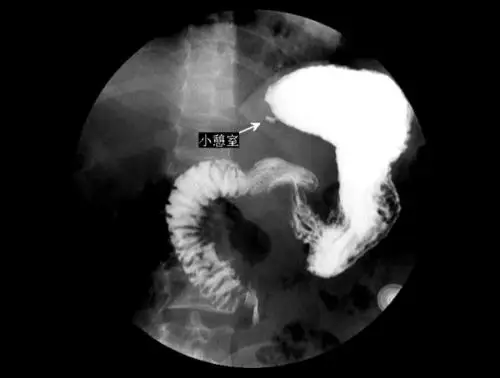

10回肠末端麦克尔憩室麦克尔憩室是在胚胎发育过程中,卵黄管退化不全

十二指肠憩室造影表现